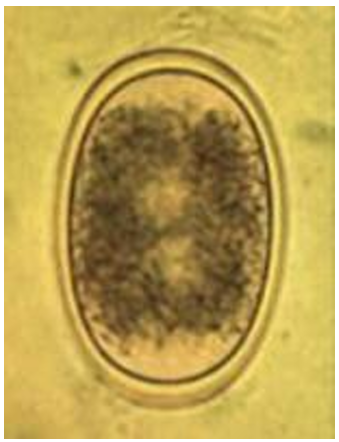

Nematodirus

ovum